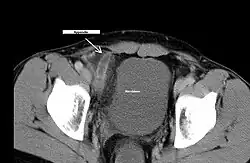

• Ultraschalluntersuchung des Bauchraumes (Kokardenformation, tubuläre Struktur, Abszess, Ausschluss anderer Erkrankungen): Als spezifisches Zeichen für eine Appendizitis gilt ein maximaler Außendurchmesser der Appendix von mehr als 6 oder 7 mm,[10] wobei ein größerer Durchmesser spezifischer ist. Die entzündete Appendix ist zumindest teilweise rund im transversen Schnittbild und nicht kompressibel. Ein Appendikolith ist ebenfalls spezifisch für eine Appendizitis, unabhängig vom maximalen Außendurchmesser der Appendix.[11] Sekundäre Zeichen der Appendizitis sind eine Wanddicke von mehr als 3 mm, ein Halo wegen eines Ödems und vermehrt ödematöses mesenterisches Fett.[12]

• Computertomographie (CT)